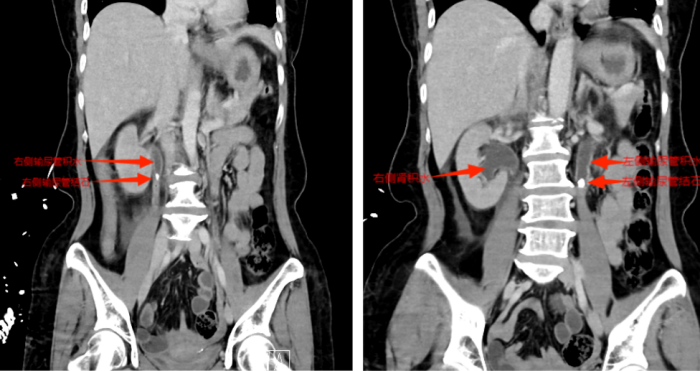

等到第二天送医时,张小华血压已降至78/42mmHg(血压<90/60mmHg称为休克血压),CT结果显示其双侧输尿管结石引发尿路梗阻,导致尿源性脓毒血症合并脓毒性休克。医院立即启动MDT多学科诊疗,泌尿外科一区主任傅发军带领团队紧急在急诊ICU实施床旁输尿管支架置入术,迅速解除梗阻,经抗感染等综合治疗,患者最终转危为安。目前,张小华已康复出院,择期再返院处理双侧输尿管结石。

CT显示双侧输尿管结石、肾积水